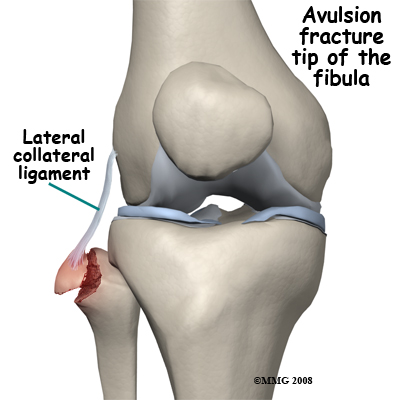

XRAYS |

AP and Lateral views

Avulsion fractures are common and easily missed. This may involve the lateral epicondyle, a Segond capsular avulsion or occasionally there is a tell tale avulsion of the tip of the fibular head indicating distraction of the lateral ligaments, this is termed the "Arcuate sign".